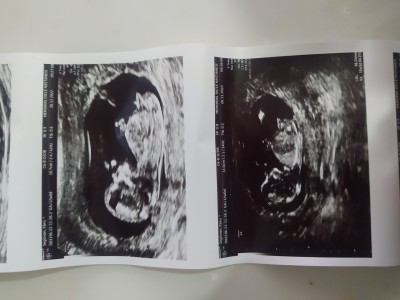

Kızlar doktor söylemedi duruştan dolayı göremedim dedi sizce ne cinsiyeti

Gebelik haftası 12+0